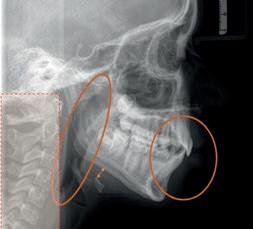

TENDO POR BASE A MINHA EXPERIÊNCIA CLÍNICA NO ACOMPANHAMENTO DE DOENTES CRÓNICOS, NEUROLÓGICOS E OUTROS, VENHO FALAR DE UMA ABORDAGEM INOVADORA. NÃO É UM TRATAMENTO, PORÉM, POR VEZES, APARENTA. TUDO COMEÇOU POR ESTA SUGESTÃO: ANTIGAMENTE NÃO EXISTIAM DENTES TORTOS?

Quando tudo começa? Num inverno, numa primavera ou basta nascer? Quase todos os bebés nascem com a capacidade de respirar pelo nariz. O que fará esse bloqueio? No desenvolvimento, a disfagia, por exemplo, é comum no paciente com ventilação predominantemente oral. Na roncopatia estão associadas, além da respiração oral, enurese noturna, agitação, sonolência diária e alterações cardiovasculares. Os pacientes acompanhados e tratados pela ortopedia funcional dos maxilares com foco na normalização de respiração são colaborantes. A principal causa dessa colaboração é o conforto que sentem e a melhoria da qualidade de vida. A ortopedia funcional dos maxilares promove a reabilitação neuro-oclusal. A remodelação das arcadas dentárias, a posição adequada da língua e o selamento labial são três premissas que mudam a vida dos pacientes.

O respirador oral inicia um ciclo de excesso de respiração que irá condicionar a resposta do anel de Waldeyer, o ritmo cardíaco, a posição da cabeça na coluna, membros inferiores e pescoço. A rotação da cabeça para melhorar a capacidade respiratória quando a boca está aberta tem implicações severas intraorais. A língua assume uma posição baixa e o desenvolvimento das arcadas acontece ou não. Quando os lábios não estão selados, a contração dos bucinadores é maior e o sorriso fica automaticamente mais estreito. Quando os dentes não têm os contactos corretos com os antagonistas, a mastigação torna-se lenta ou mais ainda extremamente rápida ou por esmagamento lingual. A cascata de acontecimentos acontece e vai acontecendo de tal forma discreta e silenciosa que a perceção das alterações já é considerada normal.